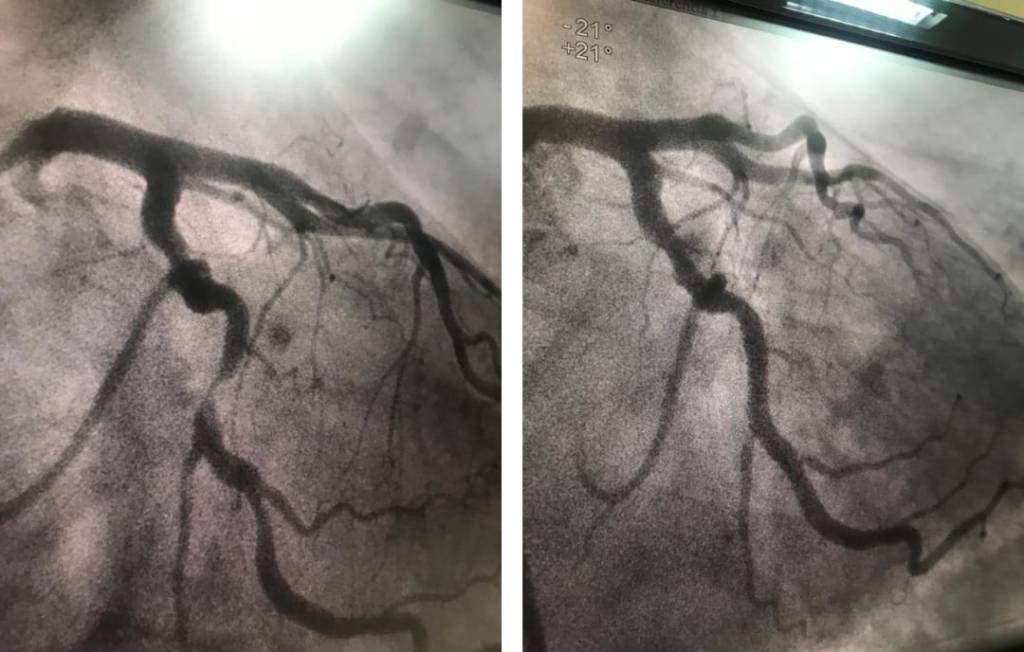

El pasado sábado 26 de agosto tuve por la tarde un golpe de dolor en el pecho y ambos brazos, que se disipó en unos minutos. Me encontraba en Toluca, en el marco de la Feria Internacional del Libro del Estado de México (FILEM), atendiendo el estand de la casa editora de mi querido Eduardo Villegas Guevara, Cofradía de Coyotes. No le di mayor importancia al hecho y quedé convencido de que era un golpe de ansiedad. Un par de horas después, mientras cenaba, me volvió ese dolor, esta vez más fuerte, que me duró como quince minutos y también pasó. Llegué a mi hotel, deshice la maleta y me preparé para dormir. Sobre las once y media de la noche, el dolor regresó para no irse. Nunca he sentido un dolor tan brutal ni asfixiante. Ya no solo afectaba a mi pecho y a mis brazos, sino también a mi cuello y, al rato, a mis antebrazos. Seguí sin darle importancia, pasé por el baño, hice ejercicios de respiración e intenté en vano conciliar el sueño en varias posturas diferentes. Comenzaron a dolerme las manos y ya entré en alerta. Busqué en internet, tomé conciencia de lo que me pasaba. Con calma rehice mis maletas, me puse ropa cómoda y bajé a la recepción. A las tres de la madrugada estaba llamando a la ambulancia. A las cuatro ingresé por urgencias al Centro Médico Adolfo López Mateos de Toluca... El lunes fui sometido a una angioplastia mediante la cual me implantaron un stent, dispositivo consistente en una malla metálica en forma de tubo que, colocado en un vaso sanguíneo, corrige el estrechamiento que pueda presentar, en la arteria coronaria izquierda, que tenía una obstrucción del 98 por ciento, quedando para mejor ocasión aunque no muy lejana intervenir la coronaria derecha, que presenta dos obstrucciones de menor consideración que la anterior. Podría parecer técnica la descripción, aunque si leyeran el informe médico...

Mi arteria coronaria izquierda antes y después de la intervención.

Fuente de la fotografía: Archivo personal de M. P.-P.